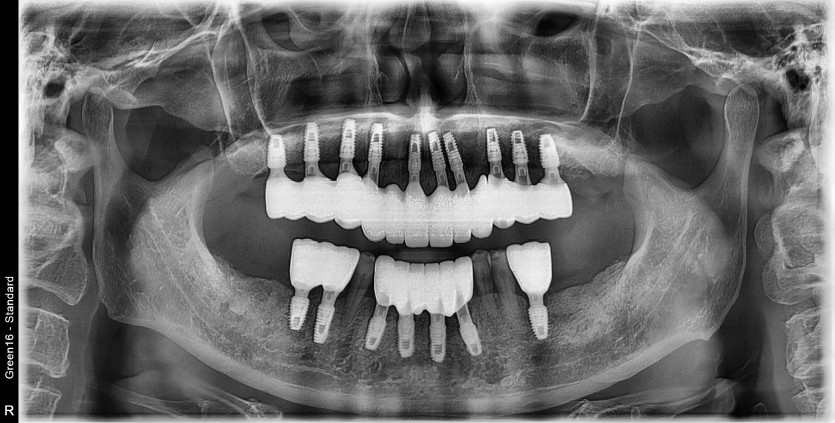

전체 임플란트 증례입니다.

17개의 임플란트로 완성하였습니다.